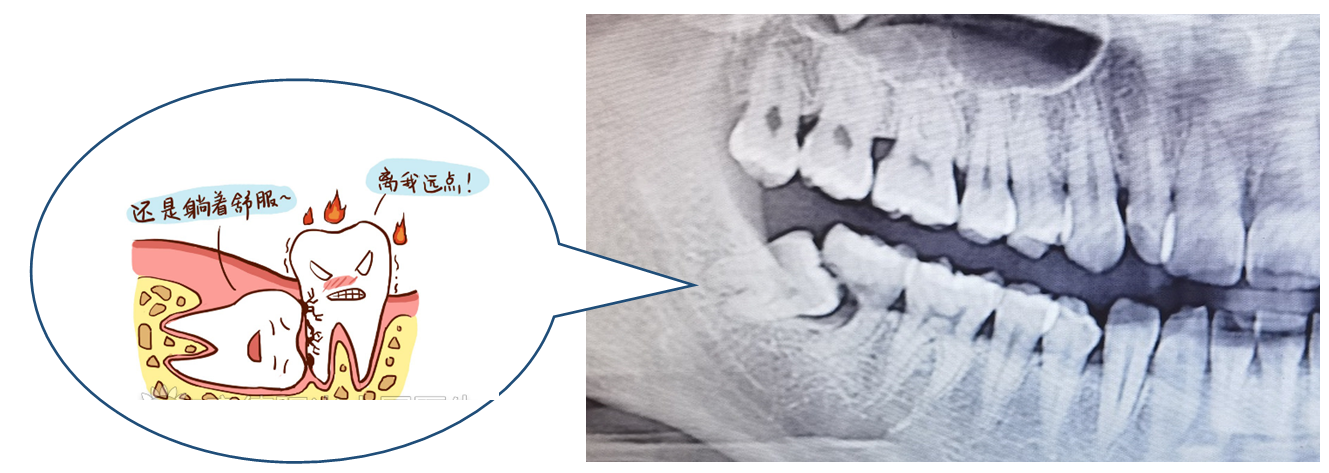

01冠周炎

冠周炎的治疗主要是清除盲袋内食物残渣和脓液等,再局部消炎止痛抗感染治疗。通常我们会先使用3%双氧水(口腔内大多是厌氧菌,双氧水可以产生氧气)和生理盐水交替冲洗,清除异物和脓液,再在盲袋内放置碘甘油等碘制剂(在此特别声明:有甲亢或对碘过敏的同志们请在治疗前告知医生)。